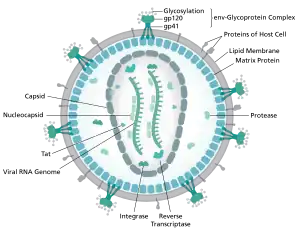

HIV is the cause of the spectrum of disease known as HIV/AIDS. HIV is a retrovirus that primarily infects components of the human immune system such as CD4+ T cells, macrophages and dendritic cells. It directly and indirectly destroys CD4+ T cells.[90]

HIV is a member of the genus Lentivirus,[91] part of the family Retroviridae.[92] Lentiviruses share many morphological and biological characteristics. Many species of mammals are infected by lentiviruses, which are characteristically responsible for long-duration illnesses with a long incubation period.[93] Lentiviruses are transmitted as single-stranded, positive-sense, enveloped RNA viruses. Upon entry into the target cell, the viral RNA genome is converted (reverse transcribed) into double-stranded DNA by a virally encoded reverse transcriptase that is transported along with the viral genome in the virus particle. The resulting viral DNA is then imported into the cell nucleus and integrated into the cellular DNA by a virally encoded integrase and host co-factors.[94] Once integrated, the virus may become latent, allowing the virus and its host cell to avoid detection by the immune system.[95] Alternatively, the virus may be transcribed, producing new RNA genomes and viral proteins that are packaged and released from the cell as new virus particles that begin the replication cycle anew.[96]

HIV is now known to spread between CD4+ T cells by two parallel routes: cell-free spread and cell-to-cell spread, i.e. it employs hybrid spreading mechanisms.[97] In the cell-free spread, virus particles bud from an infected T cell, enter the blood/extracellular fluid and then infect another T cell following a chance encounter.[97] HIV can also disseminate by direct transmission from one cell to another by a process of cell-to-cell spread.[98][99] The hybrid spreading mechanisms of HIV contribute to the virus' ongoing replication against antiretroviral therapies.[97][100]

Two types of HIV have been characterized: HIV-1 and HIV-2. HIV-1 is the virus that was originally discovered (and initially referred to also as LAV or HTLV-III). It is more virulent, more infective,[101] and is the cause of the majority of HIV infections globally. The lower infectivity of HIV-2 as compared with HIV-1 implies that fewer people exposed to HIV-2 will be infected per exposure. Because of its relatively poor capacity for transmission, HIV-2 is largely confined to West Africa.[102]